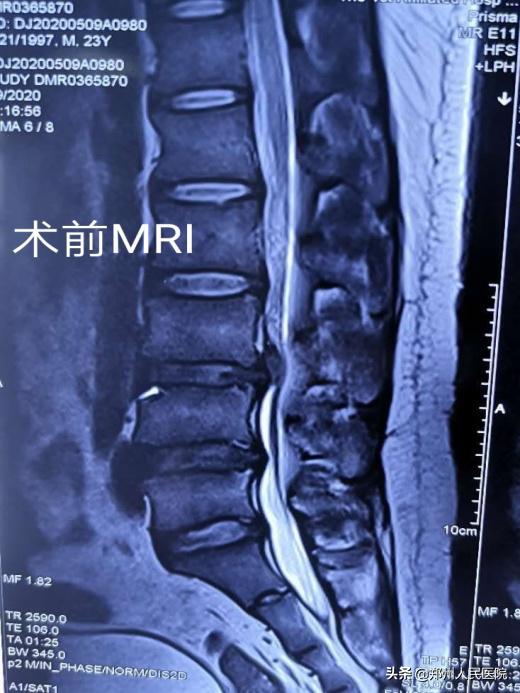

小葛立即去了省内的几家大医院看病,经过各项检查后,他被确诊存在“腰3/4椎间盘突出并髓核脱出,伴有椎管狭窄”。最让小葛纠结的是:每个医院给出的治疗方式不同,各种各样的治疗方式让小葛难以抉择。有的说可以保守治疗,有的说可以做微创手术,有的说必须进行开放手术效果才好。

田明波主任在听到小葛的情况后立即召开了全科室的病例讨论,针对患者的腰椎间盘椎管狭窄病情及患者年龄的特殊性进行反复论证,最终选择使用国内前沿的“单侧双通道UBE脊柱内镜技术”为小葛行手术治疗。

经过充分准备,对小葛实施的“单侧双通道UBE脊柱内镜术”如期举行。手术进行的十分顺利,经过一个半小时,手术成功。

在度过神经水肿期后,小葛的疼痛便消失了大半,由于手术对骨质的破坏很小,脊柱的稳定性得以最大程度的保留,手术后3天小葛就可以在腰部支具的辅助固定下行走活动,往日开朗的笑容又重新回到他的脸上。